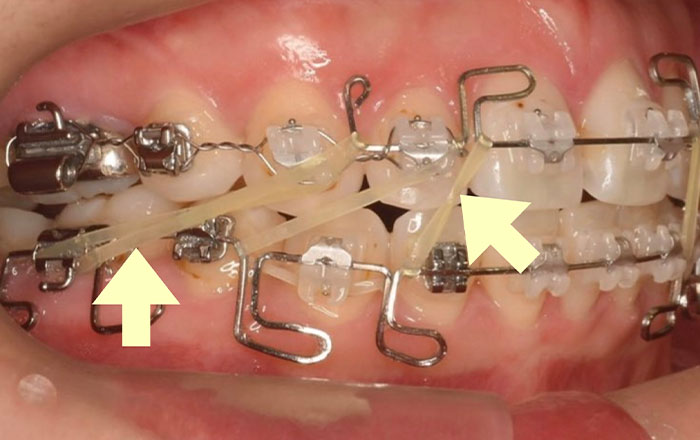

3.フォーサス

フォーサスは、バネの力を利用して、口の開閉をするたびに、【顎の位置】を、下げたい部分は後ろへ、前に出したい部分は前へ動かす装置です。

上下の歯が噛み合っていない状態は、奥歯に力がかかりやすく、ひび割れの原因になってしまうため、それを改善するためにフォーサスを入れます。

バネ式の装置なので、口を開けにくいと思われがちですが、指が縦に3〜4本入るくらいは開くので、矯正していない方と同じくらい口が問題なく開きます。

通常だと、6ヶ月〜8ヶ月程度、装置をつけます。

6ヶ月〜8ヶ月程度かかる理由は、顎を前後に動かしていく際に、顎に負担がかかると骨が削れていきますが、顎を理想の位置に動かすと新しく骨ができていきます。骨が完成する期間が6ヶ月〜8ヶ月程度かかるためです。